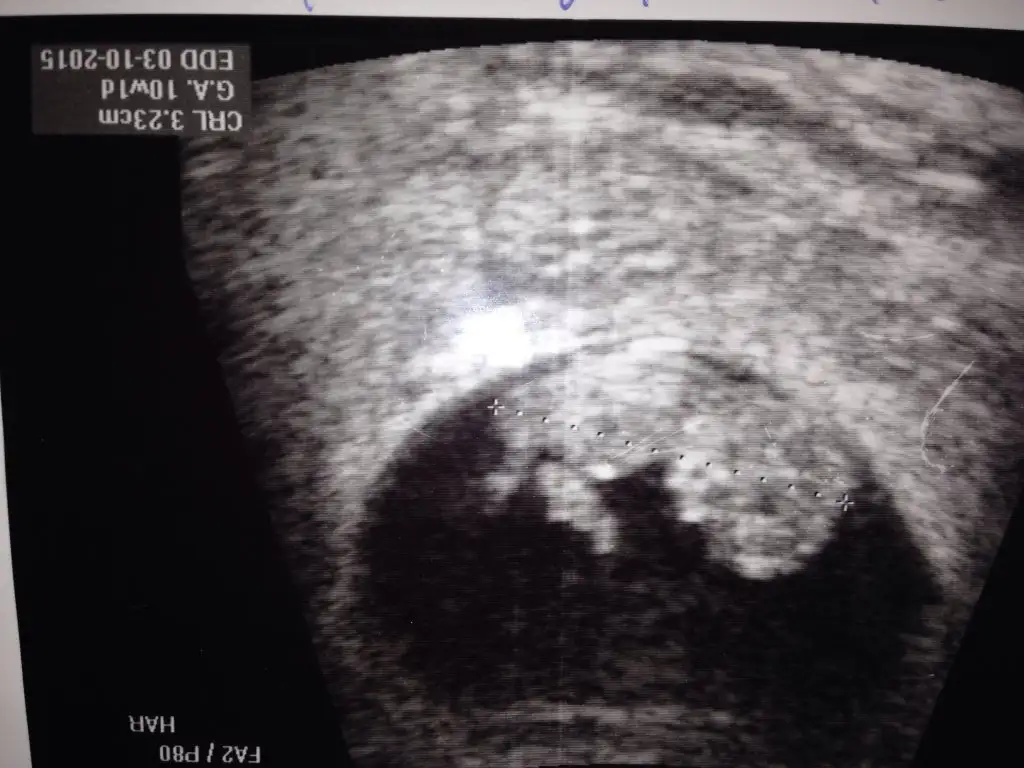

Eki Görüntüle 1504003 Kızlar Buda 10 haftalık birde buna yorum yapın yarın ultrasona giricem bakalım Hayırlısı